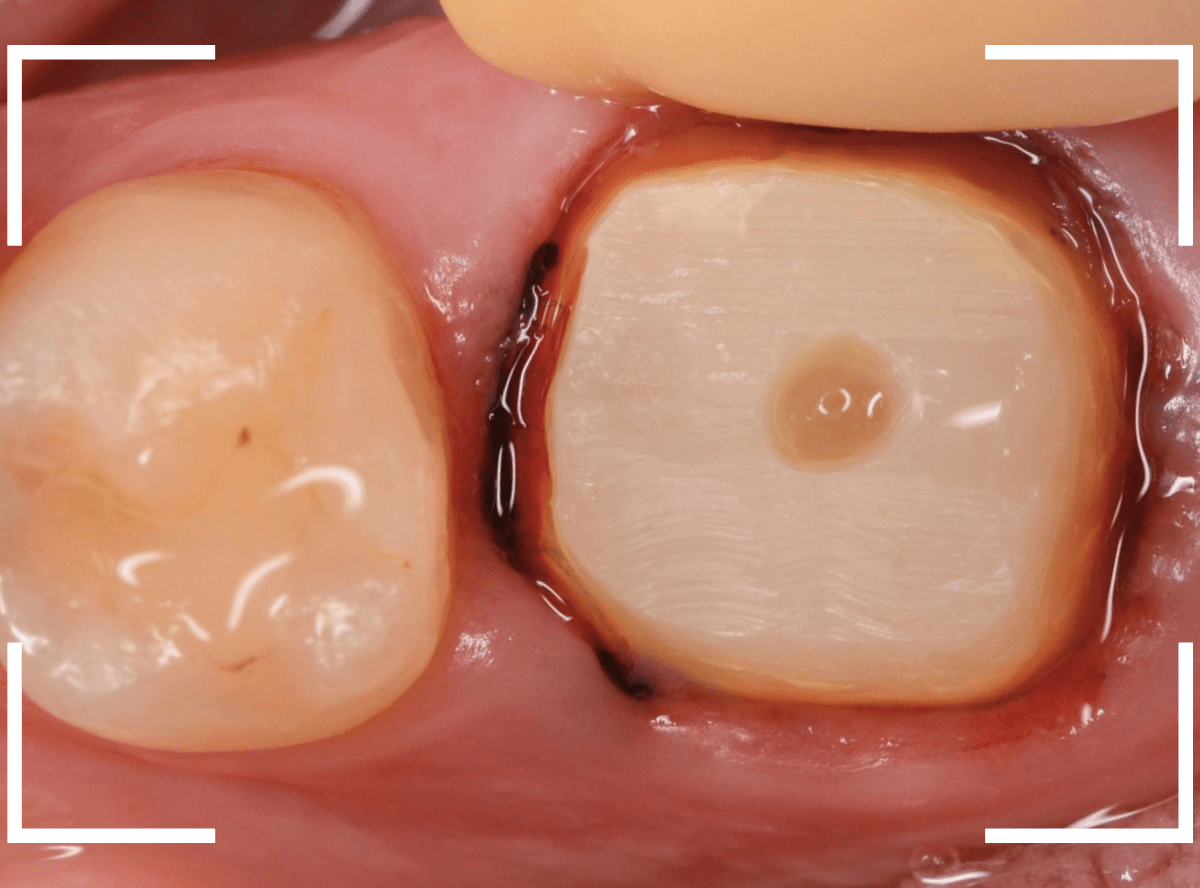

さし歯の土台の補修と、おやしらずの虫歯の処置をしたところです。

この状態で型をとります。

奥歯は歯に優しいファイバー・コアで再製し、型取りします。

模型上で精密に製作します。